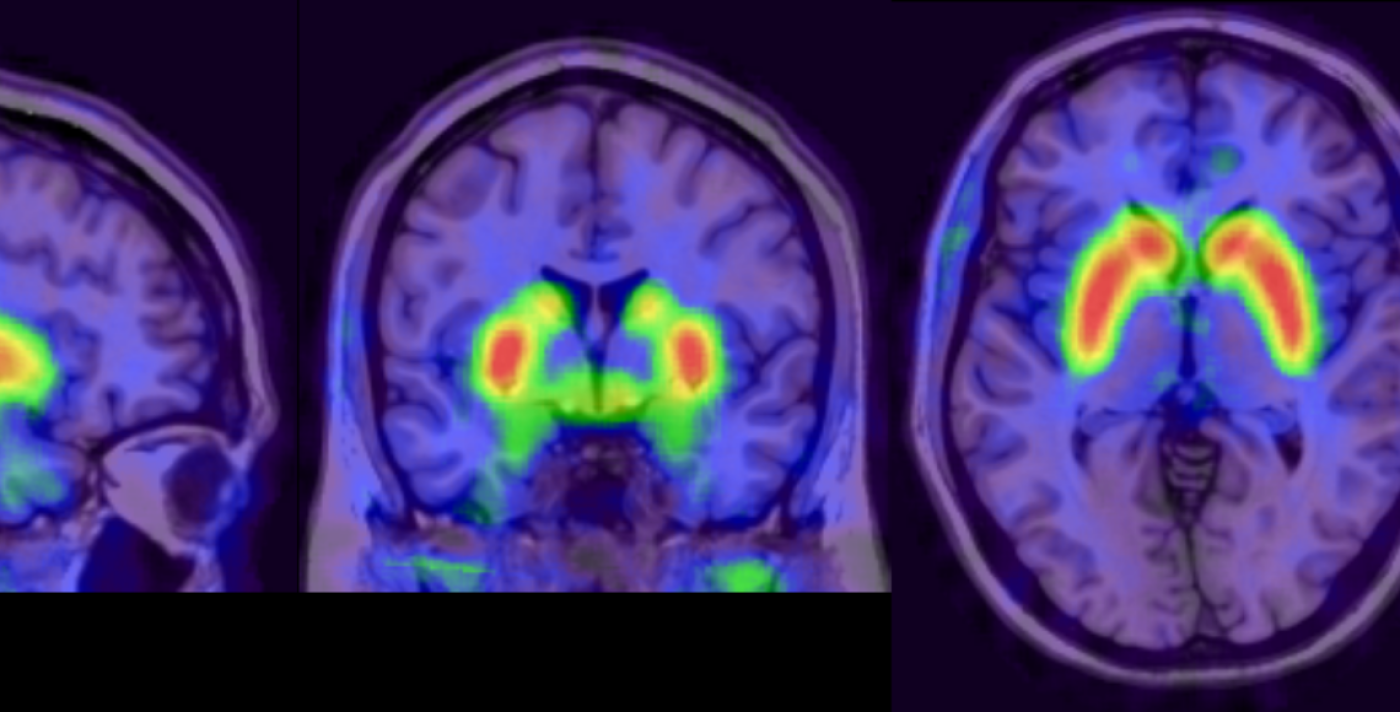

Imaging research worldwide, including some conducted at the National Institute for Health and Care Research (NIHR) Maudsley Biomedical Research Centre, have consistently shown that dopamine, a chemical messenger, is increased in a brain region called the striatum in people with psychotic disorders, as well as people at high risk for psychosis. Differences in dopamine functioning can also indicate a variation in treatment response. For example, the capacity of brain cells to produce dopamine is elevated in patients who respond well to standard antipsychotic medications but unaltered in non-responders. This is called dopamine synthesis capacity

This dopamine synthesis capacity can be measured using positron emission tomography (PET) scanners using a radioactive tracer called [18F]FDOPA. This tracer is introduced in tiny quantities into a person’s blood stream and is attracted to regions in the brain that produce dopamine and because of its radioactive characteristics, it can be visualised using PET scanning. This technique could support clinicians in identifying patients who may require alternative treatment early on.